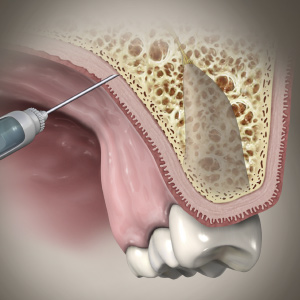

Dental Rehabilitation of the Atrophic Maxilla

Ankur Johri, DDS, MD, FACS

Friday, July 29, 2022

This Compendium eBook features a continuing education (CE) article presents important diagnostic and treatment planning principles of the All-on-4 treatment concept for the rehabilitation of the atrophic maxillary arch, and includes a case report illustrating free-hand implant placement using this treatment approach.